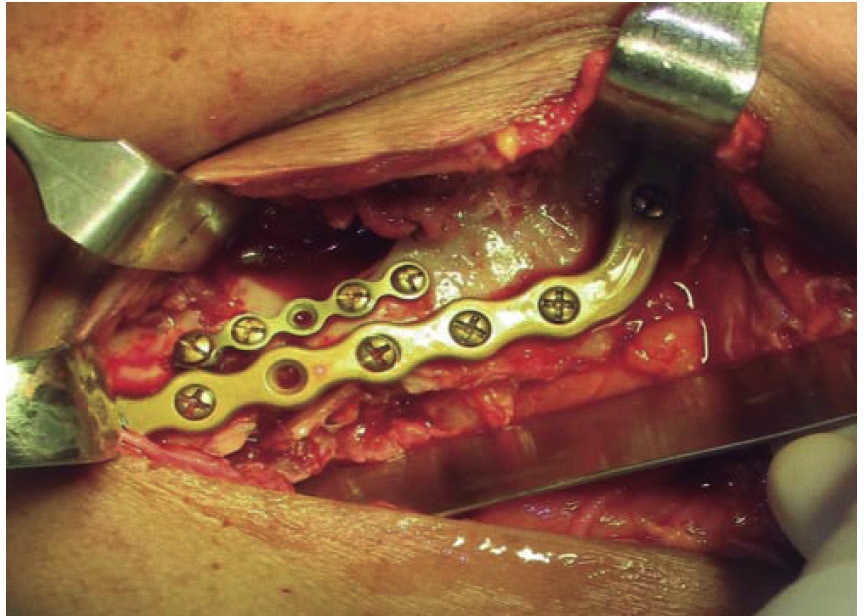

El segundo tiempo quirúrgico se realiza a los siete días mediante un abordaje extraoral. Se reduce la fractura y se fijan bordes óseos mediante una placa de reconstrucción mandibular 2.4 precontorneada (Figura 6). Previo al cierre de los tejidos se corrobora estabilidad oclusal y se retiran los arcos barra (Figura 7). El paciente permanece hospitalizado por siete días, con buena oclusión, adecuada cicatrización, se retiran puntos de sutura, se toma estudio de control y se otorga el alta médica. No acude a controles por encontrarse privado de su libertad.

Se inicia tratamiento terapéutico de inmunización, antibioticoterapia, analgesia, extracción de focos sépticos y lavados mecánicos de la herida. La paciente no cuenta con prótesis ni parcial ni removible por lo que para establecer la relación intermaxilar y altura facial se confeccionan férulas de Gunning (Figura 13). A los diez días del tratamiento inicial se encuentra con adecuada cicatrización a nivel alveolar, con presencia de secreción no fétida a nivel de herida mandibular y se procede a realizar el segundo procedimiento mediante un abordaje extraoral con una placa de reconstrucción mandibular 2.4 y una placa 2.0 para un segmento óseo (Figuras 14 y 15). Se otorga el alta, acude a valoraciones periódicas con buena cicatrización (Figura 16), y adecuada movilidad mandibular. A las tres semanas posteriores a la reconstrucción se indica a la paciente iniciar tratamiento protésico para su rehabilitación.

En los tres casos presentados se inicia con valoración cardiopulmonar, manejo de vía aérea, control hemodinámico, ventilación, discapacidad neurológica y daños específicos.9-11 Con la exploración física determinamos la extensión de daño en los tejidos, presencia de orificios de entrada y salida para descartar la presencia de bala al interior en una cavidad o tejido (caso 2). El manejo maxilofacial se inicia con desbridaje conservador, lavado, extracción de restos radiculares, sutura y estabilización oclusal. La reducción y fijación de las fracturas (caso 1 y 3) se realizó en un segundo acto quirúrgico con placas de reconstrucción. En los casos expuestos se observó una buena evolución, una cicatriz ósea favorable y la necesidad de continuar con una rehabilitación oral mediante prótesis o implantes osteointegrados. Las complicaciones y secuelas son comunes y surgen por lo general a causa de la severidad de las lesiones iniciales, retraso en el tratamiento por riesgo vital o estado sistémico del paciente.